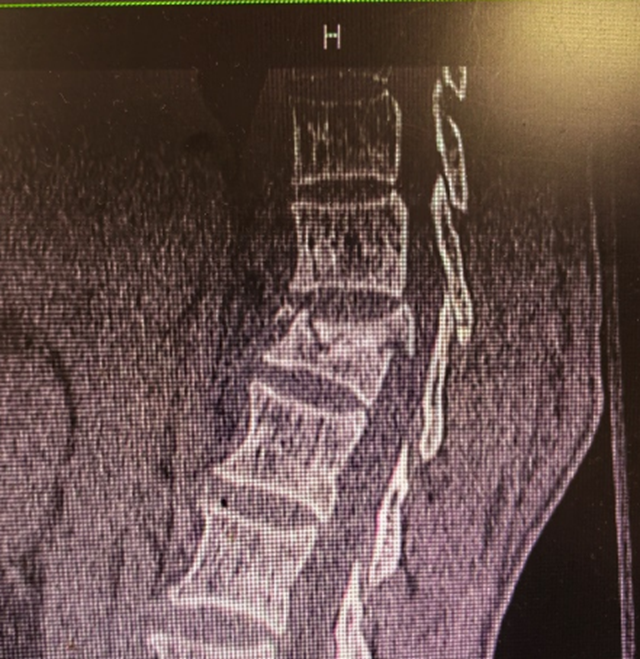

被发现后,张大妈被紧急送到了西南医科大学附属中医医院城北急诊科救治,初步诊断为“胸12椎体爆裂骨折并截瘫”,转至骨伤科脊柱·骨肿瘤二组进一步治疗。

陈波主治医师接诊后,查看急诊CT结果,提示张大妈胸12椎体爆裂骨折、椎体爆裂、椎管占位明显,大小便失禁,双下肢不全瘫,全科讨论后,需行急诊手术治疗。

迅速开启急救绿色通道,术前准备就绪后,罗琳副主任医师、陈波主治医师为张大妈实施了“经后路胸12椎体骨折复位+椎管减压+植骨融合内固定术”,历时两个小时,手术顺利完成。医务人员在进行脊髓损伤抢救的黄金时间内,为张大妈解除了神经压迫、稳定了脊柱,为损伤神经恢复创造了条件。